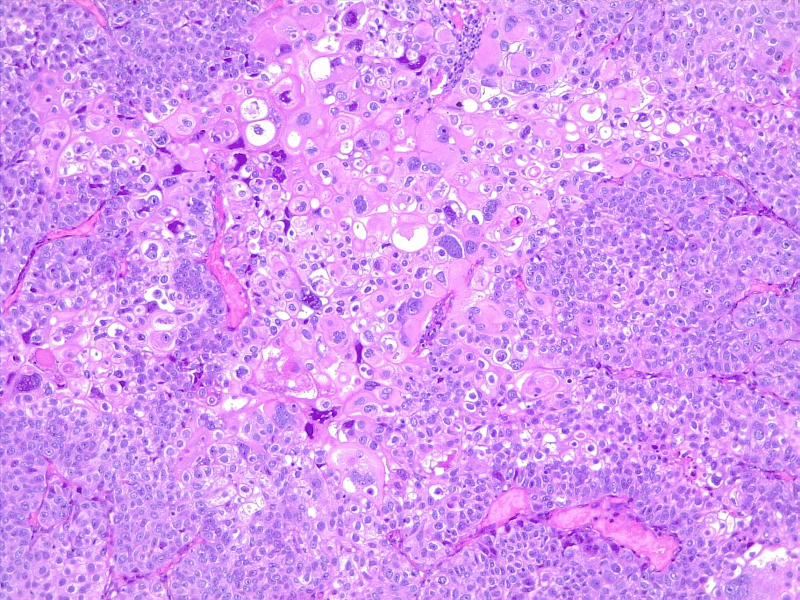

Urothelial carcinoma, perineural invasion

圖4: 尿路上皮癌,神經(jīng)周圍浸潤(rùn)。10x H/E。醫(yī)學(xué)博士 Fabiola Farci 供稿